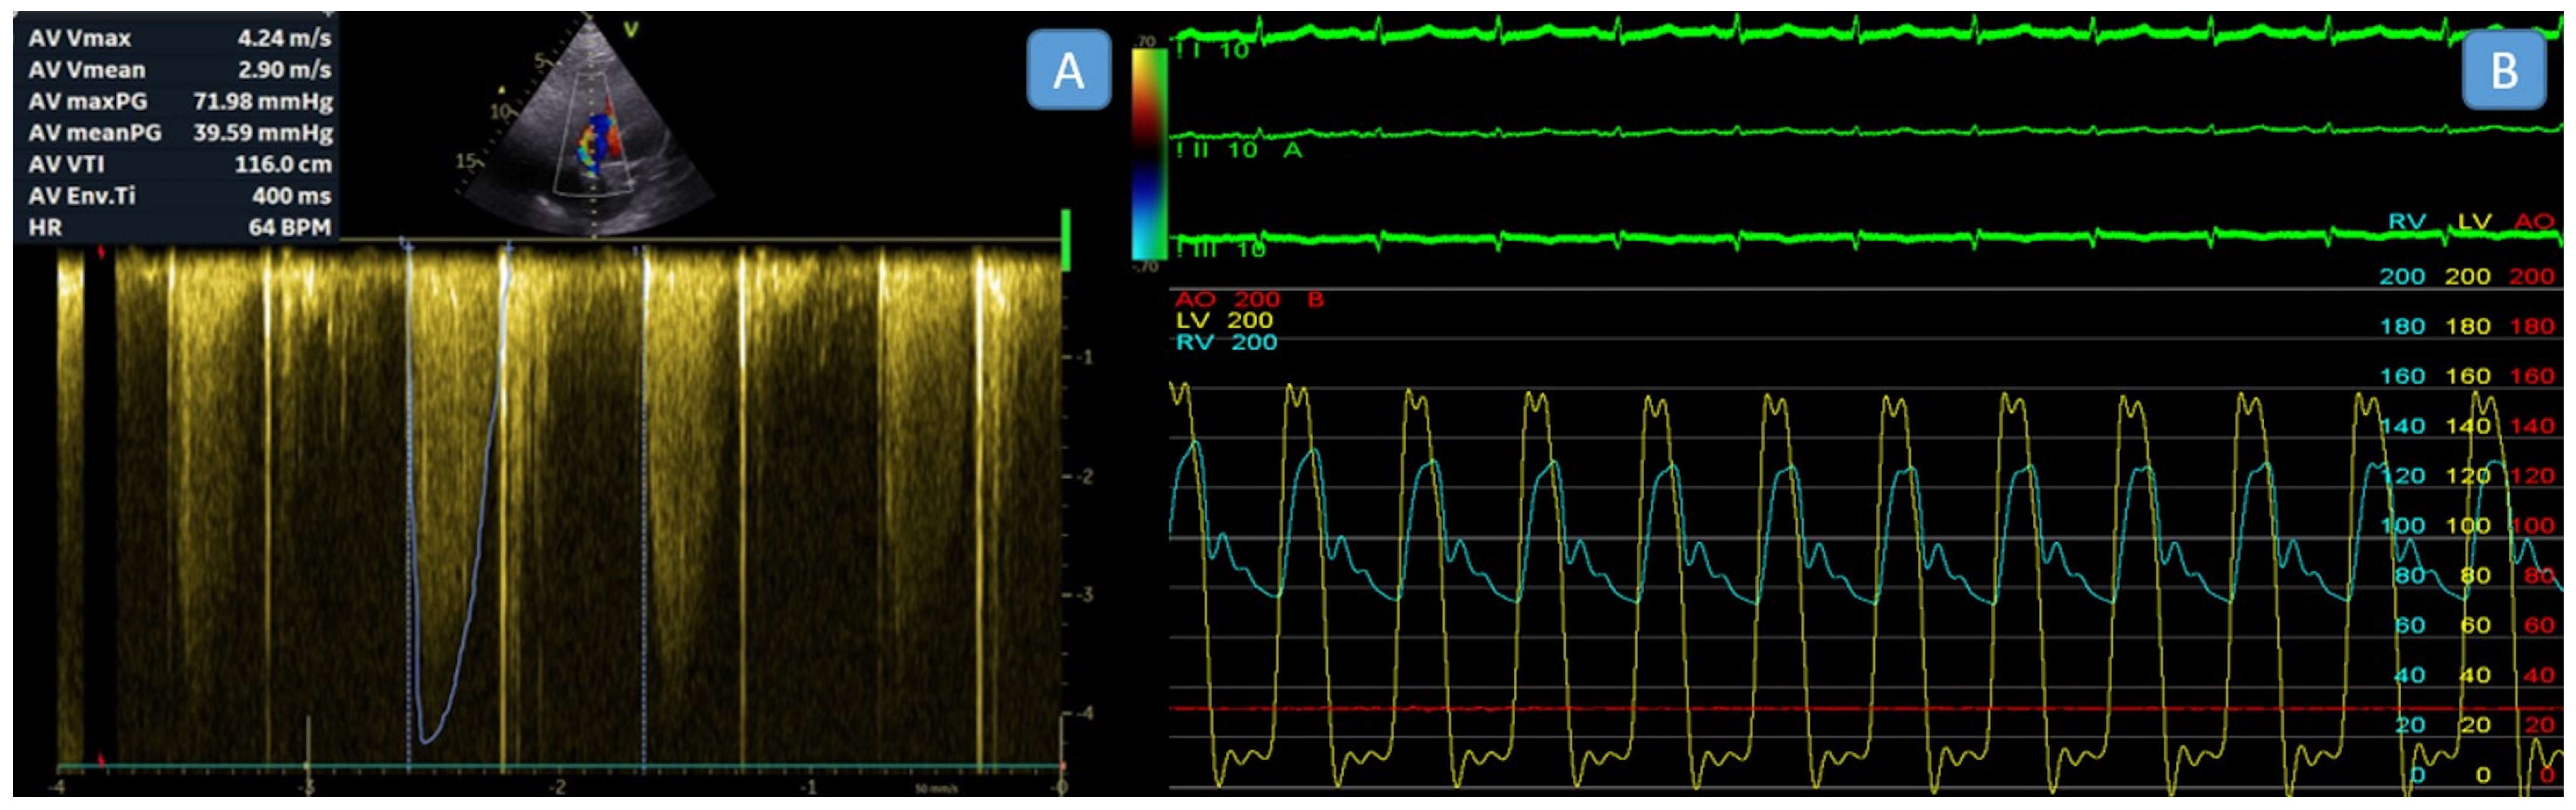

| Aortic valvular gradient, peak, mmHg | 77 ± 13.1 |

| Aortic valvular gradient, mean, mmHg | 44.2 ± 8.9 |